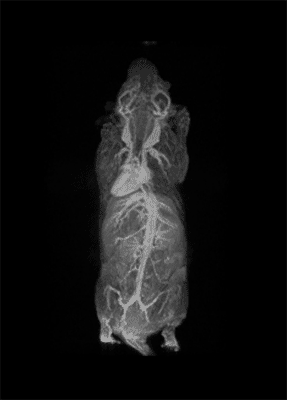

The possibility to use complementary imaging modality was our task in the last 10 or so years. And this changed quite drastically the structure of our group, because we have to get users quickly used to the basic principles in order to have efficient imaging reporter for the other imaging modalities.

So, our students now pass from one imaging modality to another to get used to the different classes of imaging reporter agents.

I think that the main direction we are putting our efforts into is one way to get more insight into metabolic imaging. To know the metabolic processes that occur at a cellular level is the way to really see the functioning of cells.